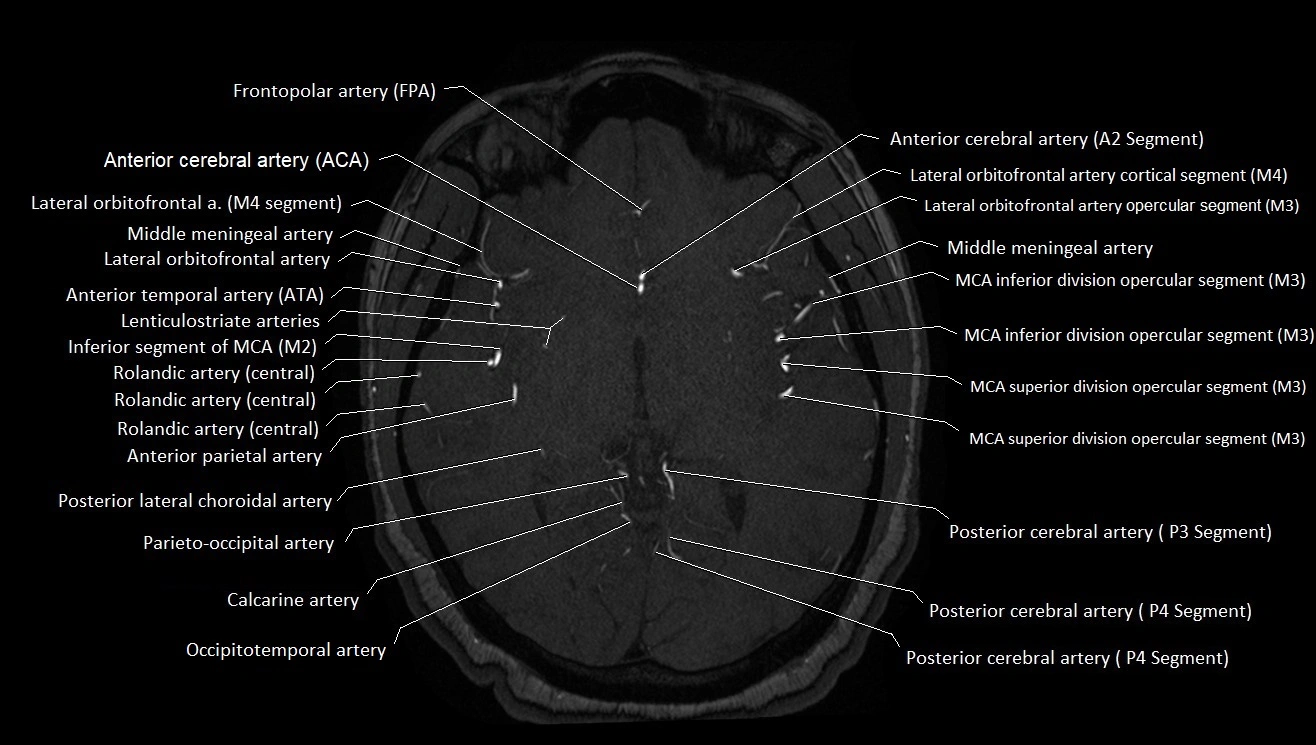

MRI images

image

CT images